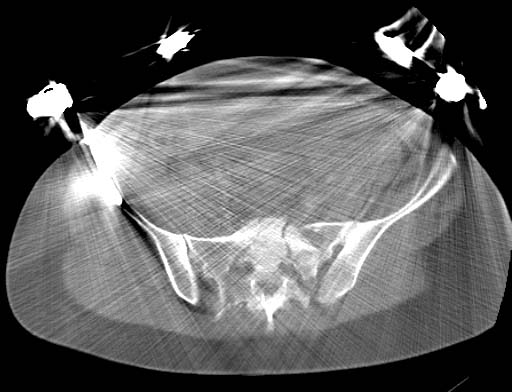

Acetabular CT - Click to Magnify